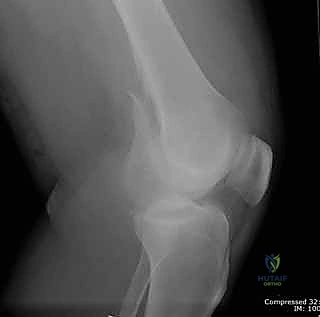

- الأشعة السينية (X-Rays): أخذ صور من زوايا متعددة (أمامي خلفي، وجانبي) لتحديد موقع الكسر ونوعه.

- الأشعة المقطعية (CT Scan): وهي ضرورية جداً في كسور عظم الفخذ البعيدة، خاصة إذا كان الكسر يمتد إلى داخل مفصل الركبة (Intra-articular fractures). تساعد الأشعة المقطعية الدكتور هطيف على بناء نموذج ثلاثي الأبعاد للكسر، مما يسهل التخطيط الجراحي وتحديد أماكن وضع المسامير بدقة.